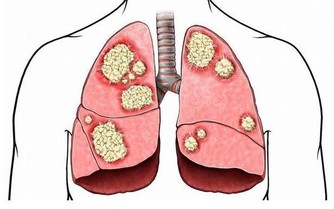

中醫理論認為: 氣血不通暢,則會疼痛。而其主要有兩個原因,一是老人年本身體虛,自身調節能力較弱,再加如果受了風寒,氣血則會更不通暢。如果不及時調整,氣血不通之後,隨之而來的比如心臟病、等各種器質性的病變。